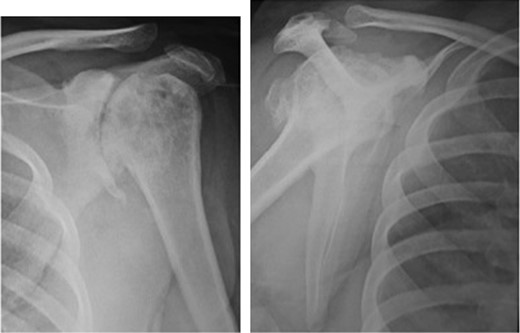

We further evaluated the patient using radiographs of the shoulder (Fig. 2) and thumb (Fig. 3) which confirmed our suspicion of neuropathic arthropathy. To exclude Milwaukee shoulder as a cause of the severe changes observed on the shoulder radiograph, we performed an MRI of the shoulder which revealed an intact rotator cuff (Fig. 4). Further, due to the associated neurological symptoms in the left upper limb, we performed an MRI of the cervical spine (Fig. 5) to identify any underlying neurological pathology. This MRI revealed a multi-level cervical syringomyelia.

Antero-posterior and scapular radiograph of the left shoulder joint showing severe reduction in glenohumeral joint space, slight superior subluxation of the humeral head, severe subchondral sclerosis and osteophytic changes, subchondral cysts and change in shape of the humeral head. Loose bodies were also present.